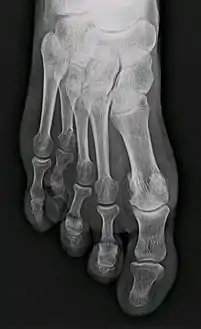

![]() مسح أشعة إكس يظهر قصر الإصبع الوراثي الذي يتضمن عضمة المشط الرابعة. مسح أشعة إكس يظهر قصر الإصبع الوراثي الذي يتضمن عضمة المشط الرابعة. | |